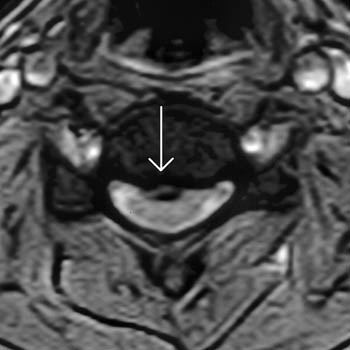

![]() |

Cervical Spine |

|

Upright Neutral |

Upright Extension |

Unsuspected

Disc Herniation in Extension |